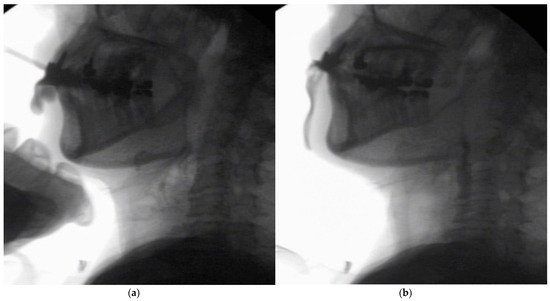

In the seated position, spoon-feeding was infeasible and bolus transport did not occur; furthermore, anterior–posterior tongue movement caused most of the food to dribble out of her mouth. After placing food on top of her tongue using a tube-fitted syringe, most still dribbled out of her mouth (Figure 1a); however, a proportion was transported into the pharynx (Figure 1b). Furthermore, after placing food at the back of her tongue with the patient reclined at 30°, a small amount still dribbled out of her mouth; however, the patient could swallow without aspiration (Figure 2). After increasing the amount placed in her mouth at one time to 7 mL, more food dribbled out of her mouth (Figure 3); additionally, there was a decreased amount transported to the pharynx. When 5 mL of a moderately thick paste was placed in her mouth, none of it dribbled out; however, slight silent aspiration was present (Figure 4). There were no particular issues observed due to peristalsis from the upper esophagus to the stomach.

Figure 3.

The patient was reclined at 30° for the administration of 7 mL of an extremely thick paste. Even when the food was placed in the retromolar area, most of the food dribbled out of her mouth (▲) upon triggering her swallowing reflex.

Figure 4.

The patient was reclined at 30° for the administration of 5 mL of a moderately thick paste. There was delayed triggering of the swallowing reflex; moreover, silent aspiration occurred (▲).